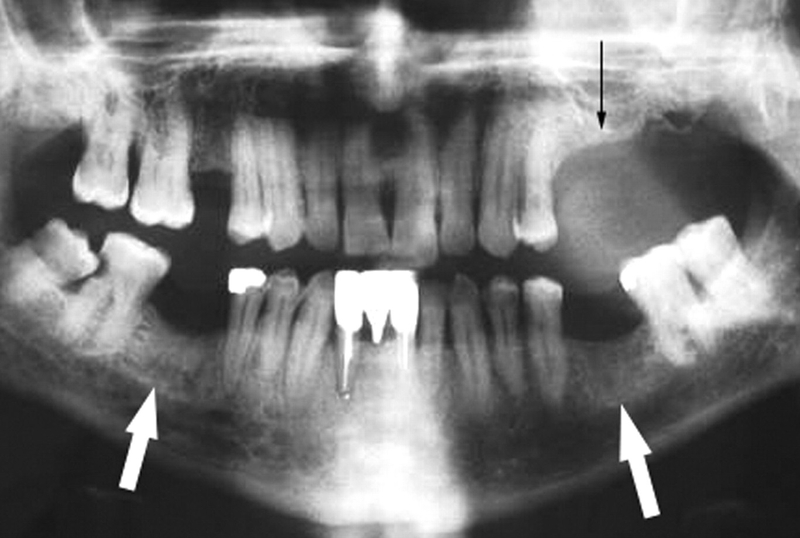

Hoại tử xương hàm là một dạng hoại tử xương có thể đến từ nhiều nguyên nhân như do xạ trị, do các bệnh lý nha khoa không được điều trị kịp thời, do biến chứng hậu covid…Một trong số những nguyên nhân gây chú ý nhất là hoại tử xương hàm do Bisphosphonate bởi số lượng bệnh nhân dùng thuốc ngày ngày càng gia tăng. Bài viết này sẽ gói gọn những điều bạn cần biết về tình trạng xương hàm hoại tử do Bisphosphonate.

Hoại tử xương hàm do Bisphosphonate là hoàn toàn có cơ sở khoa học. Xương hàm là khu vực dễ tác động và ổ xương răng của răng hàm có khả năng tái mô hình nhanh gấp khoảng 10 lần các xương dài khác trên cơ thể. Trong khi đó, thuốc Bisphosphonate lại giảm tiêu xương nhờ tác động làm giảm sự tạo mạch trong xương. Điều này làm chậm lại quá trình chu chuyển xương vốn diễn ra rất nhanh ở xương ổ răng nên đã dẫn đến hoại tử xương hàm.

Hoại tử xương hàm do Bisphosphonate có triệu chứng tương đối giống các trường hợp hoại tử xương hàm do các lý do khác. Ngoài ra các bác sĩ có thể kết hợp thêm các yếu tố nguy cơ như bệnh nhân đang dùng Bisphosphonate và không có tiền sử xạ trị để chẩn đoán bệnh. Một số dấu hiệu nhận biết hoại tử xương hàm do dùng thuốc Bisphosphonate phổ biến nhất như:

Theo Hội phẫu thuật Miệng và Hàm mặt Hoa Kỳ, quá trình tiến triển của bệnh hoại tử xương hàm do Bisphosphonate được phân ra làm các giai đoạn như: